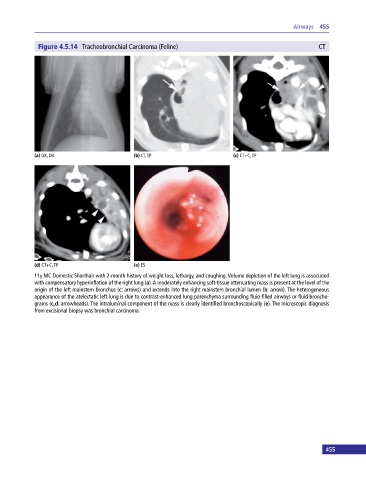

Figure 4.5.14 Tracheobronchial Carcinoma (Feline) CT

(a) DX, DV (b) CT, TP (c) CT+C, TP

(d) CT+C, TP (e) ES

11y MC Domestic Shorthair with 2‐month history of weight loss, lethargy, and coughing. Volume depletion of the left lung is associated

with compensatory hyperinflation of the right lung (a). A moderately enhancing soft‐tissue attenuating mass is present at the level of the

origin of the left mainstem bronchus (c: arrows) and extends into the right mainstem bronchial lumen (b: arrow). The heterogeneous

appearance of the atelectatic left lung is due to contrast‐enhanced lung parenchyma surrounding fluid‐filled airways or fluid broncho

grams (c,d: arrowheads). The intraluminal component of the mass is clearly identified bronchoscopically (e). The microscopic diagnosis

from excisional biopsy was bronchial carcinoma.